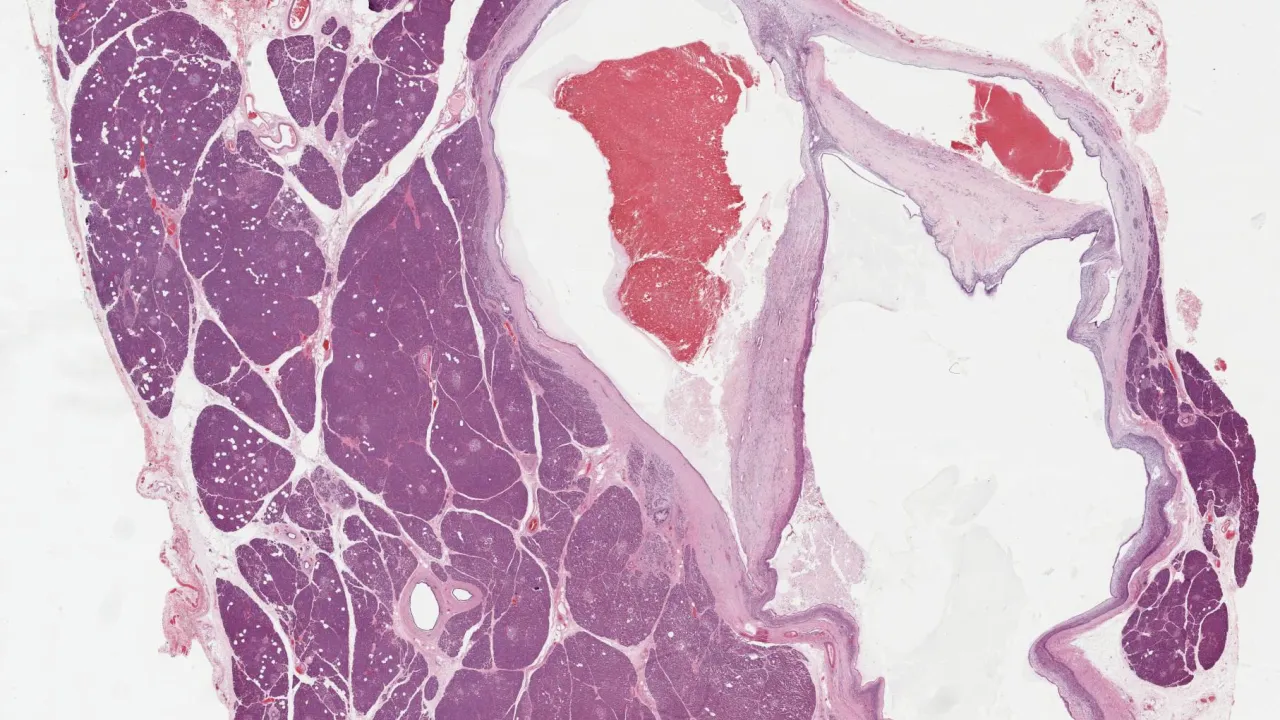

Pancreas, Intraductal papillary mucinous neoplasm